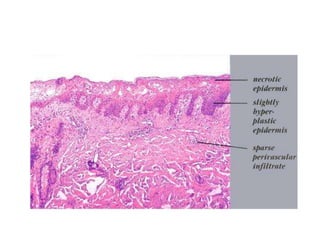

Pathology of ICD

• Variable mix of inflammation, necrosis of epidermal

keratinocytes, and mild spongiosis

• Combination of an upper dermal perivascular infiltrate of

lymphocytes with minimal extension of inflammatory cells into

the overlying epidermis, and widely scattered necrotic

keratinocytes is most typical picture

• True features of interface dermatitis are absent, and spongiosis

should be focal or absent

• Over time additional histologic findings include acanthosis with

mild hypergranulosis and hyperkeratosis

Pathology of ICD •Variable mix of inflammation, necrosis of epidermal keratinocytes, and mild spongiosis • Combination of an upper dermal perivascular infiltrate of lymphocytes with minimal extension of inflammatory cells into the overlying epidermis, and widely scattered necrotic keratinocytes is most typical picture • True features of interface dermatitis are absent, and spongiosis should be focal or absent • Over time additional histologic findings include acanthosis with mild hypergranulosis and hyperkeratosis